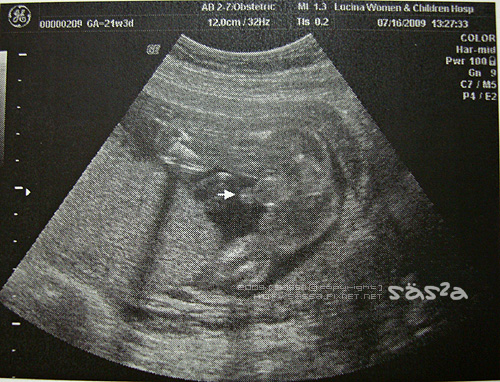

去醫院前特地叮嚀柚子泥乖乖配合醫生俗俗,讓大家看清楚你,迷想到這小子越是交代越是不配合,影像照到柚子泥時,醫生說『啊!他正趴著睡,這樣比較不容易看清楚!只有一個地方最明顯!』我想柚子泥一定氣透了有人談論著會不會翻盤的聲音,特地趴了一個超特寫姿勢,好讓大家看清楚我是男生啊!好啦!我們都知道惹,下次可以配合點嗎?

因為柚子泥趴著,這次的高層次超音波還不如上次產檢拍的超音次來的清楚@@,整個大傻眼,不過還好醫生的技術好,很努力的解釋著柚子泥所有內臟的成長情形,頭圍、腹圍、角度、脊髓、手臂、腿、胃等等,當然一切都很正常,還剛好看到柚子泥打哈欠張嘴閉嘴的好可愛。但醫生很討厭@@,說『現在正常不能保證以後也都正常,那以後都正常也不能保證他會考第一名!』真是冷笑話,哈!